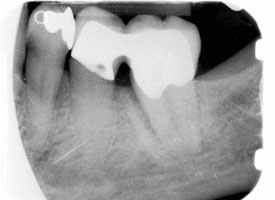

Auf dem Röntgenbild sieht man an der Vorderfläche des Zahnes einen tiefen Knochendefekt bis zur Wurzelspitze des Zahnes.